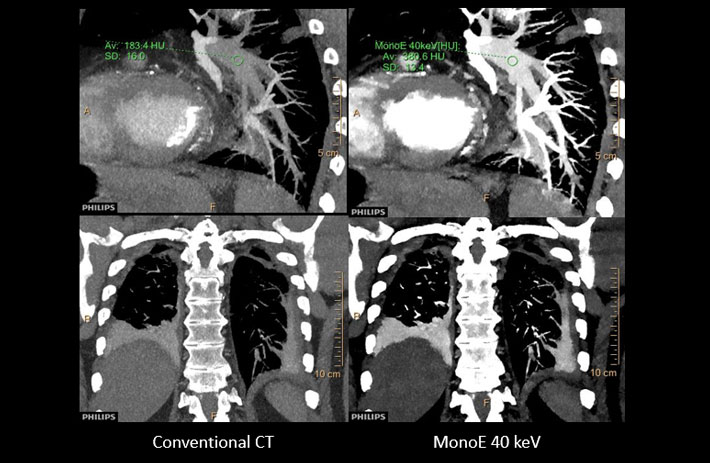

Mit dem Spektral-Detektor-CT werden Spektraldaten automatisch bei jedem Scan erfasst. Die Informationen stehen jederzeit auf der Scankonsole, der CT-Workstation sowie an jedem PACS-Arbeitsplatz zur Verfügung, sodass es nicht notwendig ist, den Patienten erneut zu scannen, bspw. wenn initial zufällige Anomalien festgestellt wurden. Dadurch profitieren Anwender durch eine höhere Diagnosesicherheit und weniger Nachuntersuchungen auf anderen bildgebenden Systemen. Unsere Fallsammlung zeigt, welchen klinischen Mehrwert der Spektral-Detektor-CT in unterschiedlichsten Anwendungsbereichen in der klinischen Routine bringt. Jede Woche gehen neue Fälle live.